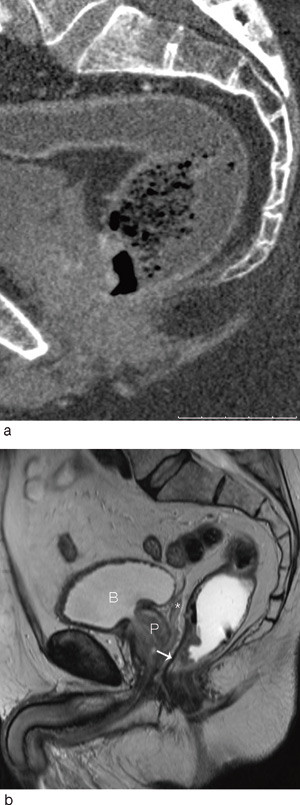

Bruk av CT i utredningen av fjernmetastaser ved kolorektal kreft er en godt etablert metode. CT-undersøkelsens rolle i den lokoregionale utredningen av rectumcancer er betydelig mer usikker. Studier fra de senere år har vist relativt dårlige resultater når det gjelder evaluering av perirektal tumorspredning, med en nøyaktighet på 52 – 74 % (6, 7, 12). Med MDCT-maskiner med minst 16 kanaler har man fått muligheten til å ta tynne bildesnitt som kan rekonstrueres i alle plan med samme gode bildekvalitet (fig 1, fig 2). Slik kan man få bilder parallelt og perpendikulært til tumors lengdeakse, analogt til MR-undersøkelsen. Det er vist at bruken av slike rekonstruerte bilder signifikant bedrer evalueringen med multidetektor-CT (13). Det finnes få studier der man har sammenliknet MDCT-undersøkelse med andre metoder ved rectumcancer, men resultatene så langt synes å være lovende (14) – (17).

Man venter snart resultater fra en ny, stor multisenterstudie i Nederland der bruk av CT-undersøkelse ved rectumcancer evalueres. I en nyere artikkel av Beets-Tan og medarbeidere refereres det til preliminære resultater som viser at MDCT er likeverdig med MR i øvre/midtre del av rectum, mens MR er overlegen i nedre del (18). I forhold til MR har CT dårligere evne til å skille bløtdelssjiktene fra hverandre i dette området, hvor subtile detaljer som 1 – 2 mm infiltrasjon kan skille en T2-tumor fra en T4-tumor (fig 3).